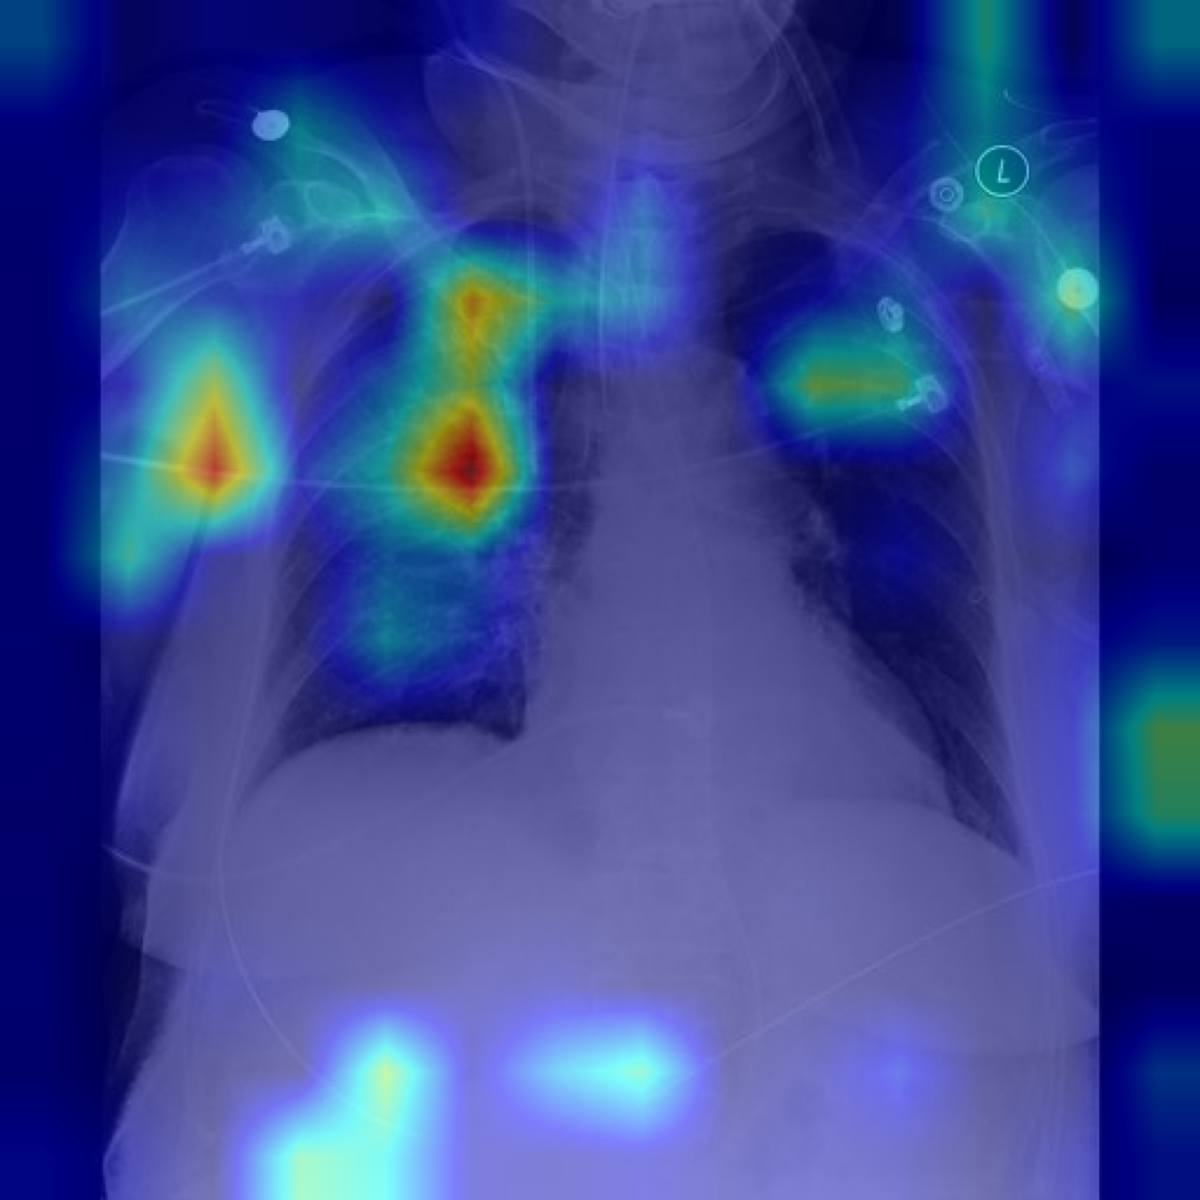

Beyond improvements in clinical accuracy, a central motivation of CEMRAG is to make the visual evidence underlying generated reports explicitly inspectable. In this section, we show how SpLiCE concepts and gradient-based explanations can be combined to reveal where the model “looks” in the image when producing specific medical terms in the report.

Table 6: Qualitative Examples with Concept-Specific Visual Explanations. Grad-ECLIP heat maps highlight image regions that influence the LLaVA-Med encoder’s matching between input images and SpLiCE concepts (highlighted in blue). The visualizations show which spatial features contribute to concept identification in the generated reports. Top row: Zero-Shot setting; bottom row: supervised fine-tuning setting.

Original Image Grad-ECLIP Activation Maps [Uncaptioned image] [Uncaptioned image] [Uncaptioned image] Endotracheal Tube Right Upper

For each case, we select SpLiCE concepts that appear in the generated report (e.g., endotracheal tube, right upper, median sternotomy, bilateral pleural). We apply Grad-ECLIP [57] to compute the gradient of the image–text similarity score with respect to the visual features used by the LLaVA-Med vision encoder. The resulting relevance map is then upsampled and overlaid on the chest X-ray as a heat map, yielding a concept-specific visualization of which regions support that term. CEMRAG-generated reports and their corresponding concept heat maps are illustrated in Table 6 for two representative MIMIC-CXR cases, one in the Zero-shot regime and one after SFT. In each example, the left column shows the reference report, while the right column shows the CEMRAG output with the relevant concept tokens highlighted. Below these reports, we display the original image together with Grad-ECLIP maps for two selected concepts. In the Zero-shot example, concepts such as endotracheal tube and right upper are both present in the generated report and exhibit Grad-ECLIP activations that concentrate along the tracheal tube and in the right upper lung zone, respectively. In the SFT example, the concept median sternotomy yields strong activation along the midline sternal wires and retrosternal region, while bilateral pleural produces strongest activation in the lower lung zones near the right and left costophrenic angles, where pleural effusions typically accumulate. Taken together, these patterns are consistent with standard radiological practice and suggest that, when a concept appears in the report, it is usually backed by visually plausible evidence in the corresponding image regions.

These concept-specific maps serve two complementary purposes. First, they allow clinicians to verify that SpLiCE-derived concepts, when injected into the prompt, are grounded in image regions that are consistent with their radiological meaning, rather than reflecting arbitrary directions in embedding space. Second, they expose failure modes in a transparent way: if a concept is mentioned in the report but its Grad-ECLIP map does not align with plausible anatomy, this discrepancy can be inspected, questioned, and potentially used to flag low-trust outputs. At the same time, this analysis remains focused on the vision component: Grad-ECLIP explains how visual encoders support individual concepts, but does not by itself reveal how the LLM composes multiple concepts into full sentences. Extending concept-level tracing to the language component remains an important direction for future work toward fully interpretable medical VLMs.